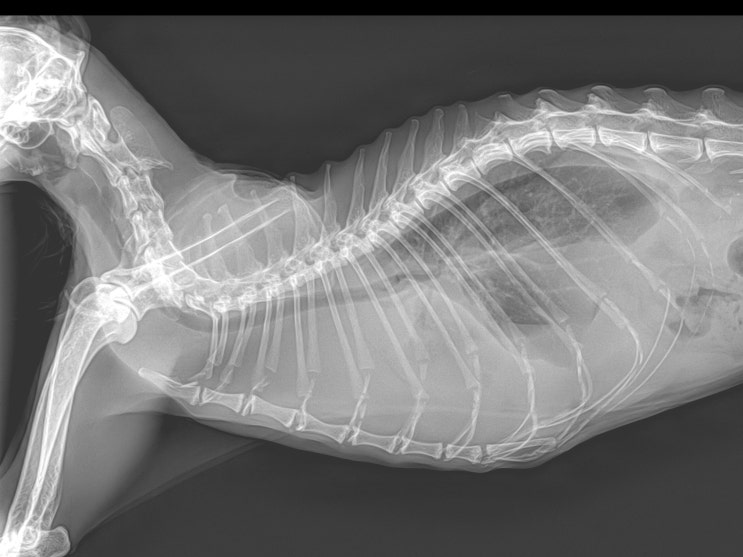

18살 고양이 호흡 이상, 곤란한 이유 / 노령묘 흉수 원인, 치료, 관리법 / 고양이 식욕 감소, 호흡수가 빠른 이유는? / 고양이 유미흉 엑스레이, 치료, 관리하는 방법

안녕하세요~ 굿파파 수의사입니다. 벌써 4 월의 마지막 일요일입니다. 행복한 미소 가득한 하루 보내세요 ...